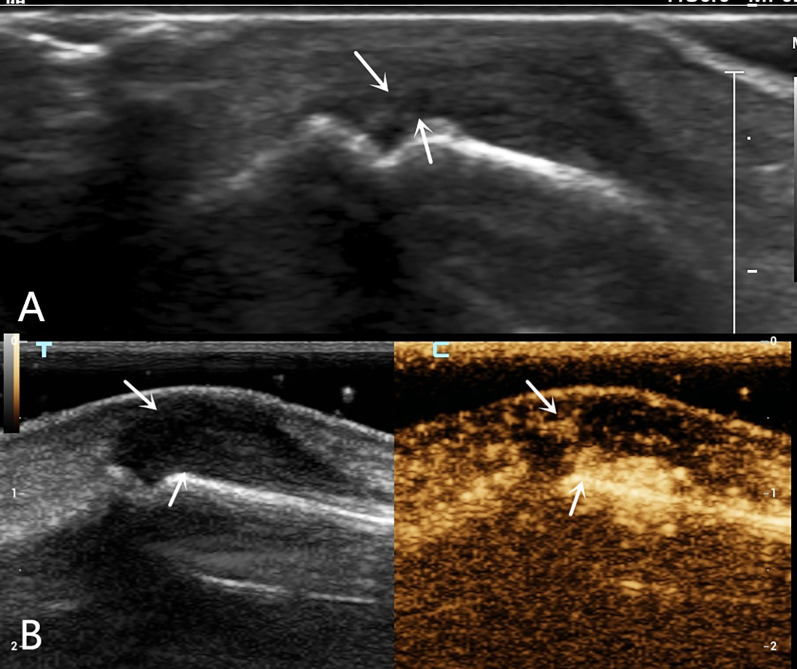

Background: By combining high-frequency and contrast-enhanced ultrasound (CEUS), the position of the severed end of a finger extensor tendon injury and the injury classification can be determined as part of a comprehensive preoperative evaluation in clinical practice. However, there have been no reports of high-frequency ultrasound combined with CEUS for the preoperative diagnosis of human finger extensor tendon injury.

Cases presentation: One case of complete rupture of the extensor tendon was diagnosed by ultrasound, which was completely consistent with the surgery; one case of incomplete rupture was ultimately confirmed clinically; and one case of distal phalangeal bone base avulsion fracture with tendon contusion and missed diagnosis on the first radiographic examination was confirmed by follow-up radiographic examination.

Conclusions: Different types of finger extensor tendon injuries exhibit distinctive contrast-enhanced ultrasonography findings. Combined high-frequency and contrast-enhanced ultrasound can accurately locate the position of the severed end of the finger extensor tendon injury before surgery while observing the contrast agent filling area to clarify injury classification, providing a reliable imaging basis for clinical practice and ultimately developing personalized diagnosis and treatment plans for patients to ensure minimal trauma and pain, as well as optimal treatment effects.